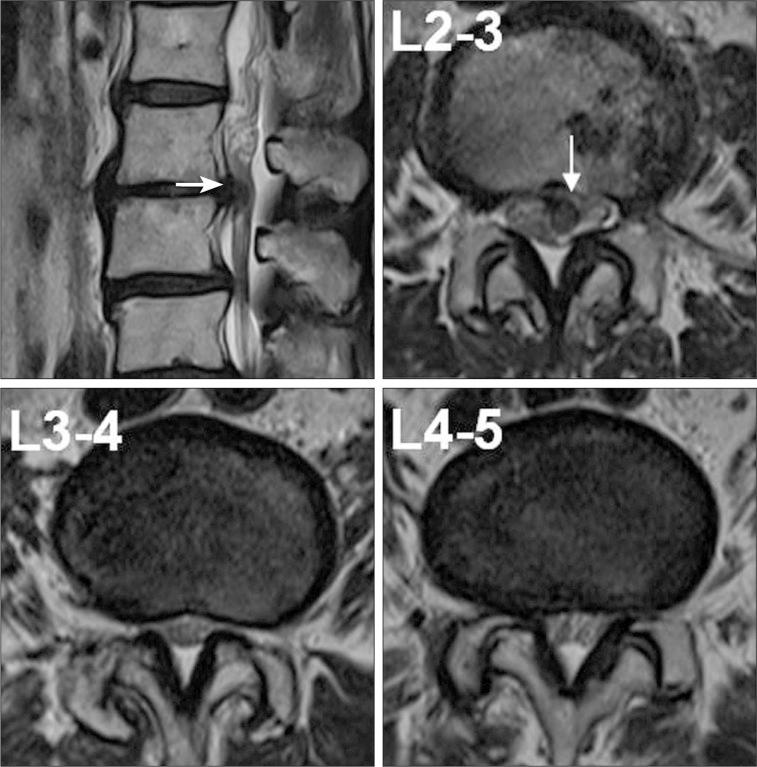

The authors report 2 cases of nerve root herniation after discectomy of a large lumbar disc herniation caused by an unrecognized dural tear. Patients complained of the abrupt onset of radiating pain after lumbar discectomy. Magnetic resonance imaging showed cerebrospinal fluid signal in the disc space and nerve root displacement into the disc space. Symptoms improved after the herniated nerve root was repositioned. Clinical symptoms and suggestive radiologic image findings are important for early diagnosis and treatment.

作者报告了2例因未识别的硬脊膜撕裂导致大的腰椎间盘突出症行椎间盘切除术后神经根疝的病例。患者在腰椎间盘切除术后出现突发的放射性疼痛。磁共振成像显示椎间盘间隙有脑脊液信号,神经根移位至椎间盘间隙。将疝出的神经根复位后症状改善。临床症状和提示性的影像学表现对早期诊断和治疗很重要。